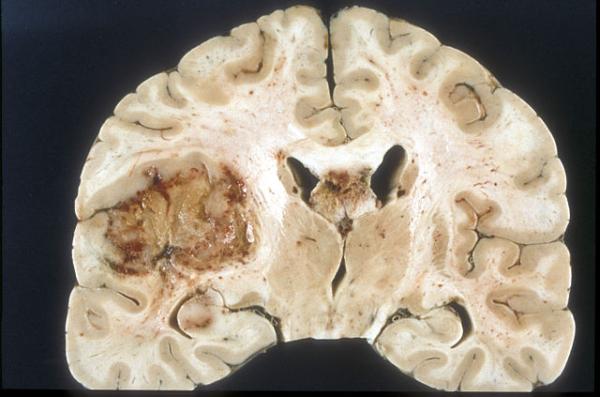

Glioblastoma multiforme (GBM), one of the most dreaded and deadly forms of brain cancer, has been on my mind recently because one of my dog-park friends was recently diagnosed with it. Characterized by aggressive growth and resistance to conventional treatments, GBM affects more than 14,000 Americans and claims approximately 10,000 lives each year. Even with intensive treatment — including surgery, radiation, and chemotherapy — the median survival time after diagnosis is 15 months, and only about five percent of patients survive beyond five years.

GBM's resistance to treatment stems from its complexity and heterogeneity. The tumor is not just one type of cancer cell; it is a collection of diverse cells, each with different characteristics. This heterogeneity allows the tumor to evade therapies targeting a single marker. Efforts to harness the immune system to attack GBM have often been thwarted by the tumor’s ability to adapt and survive. For example, therapies targeting the epidermal growth factor receptor variant III (EGFRvIII) — a key protein often found in GBM cells — have shown only limited success due to the tumor’s variability.

Adding to the challenge, GBM’s location in the brain or spinal cord makes surgical removal difficult, and the blood-brain barrier limits the effectiveness of many drugs because it prevents them from getting to the site of the tumor. Despite decades of research, effective treatment of GBM is rare.